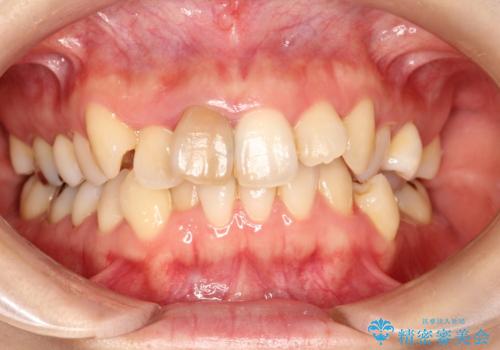

ハーフリンガル ワイヤー矯正による非抜歯・過蓋咬合の治療

- 非抜歯、大臼歯遠心移動による臼歯関係の是正・過蓋の改善をハーフリンガル・ワイヤー矯正にて計画した。

現在過蓋咬合の非抜歯治療はマウスピースで行うのが第1選択といっても過言ではありません。